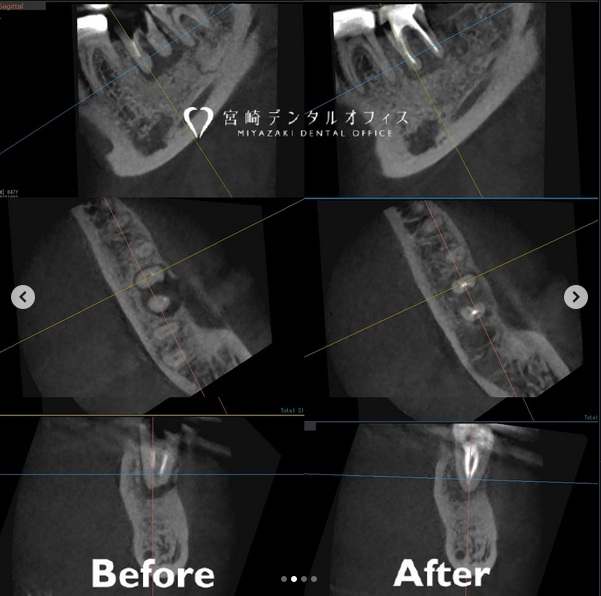

この患者様の症例は “他院では治療できないと言われた” という主訴で、たしかに左下7は精査したところ保存不可でした。

そこで、後ろにある親知らずを抜歯して、歯牙移植(自家歯牙移植=ご自身の歯を使用して移植)を行うこととなりました。

経過